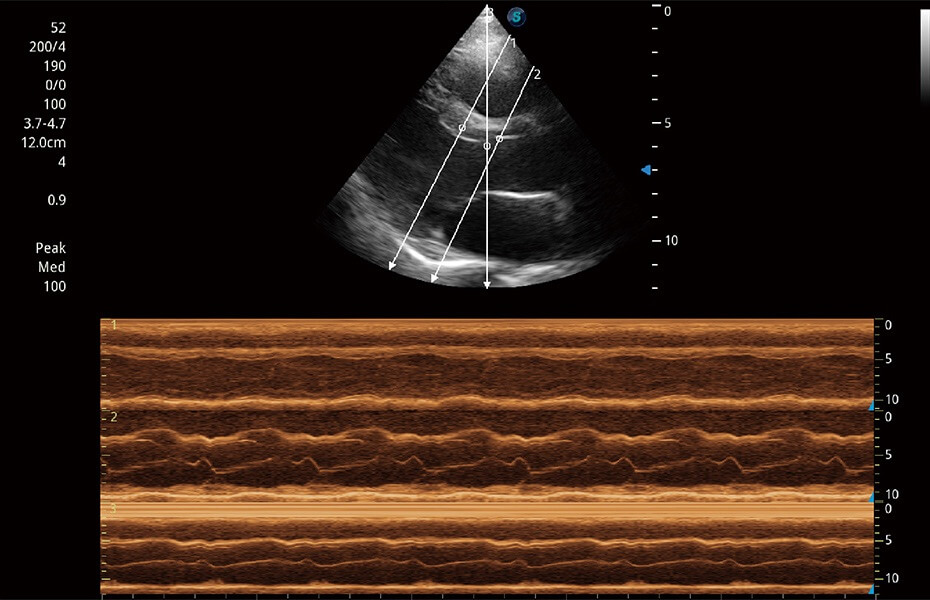

ProPet 60 作為一款高端臺(tái)式動(dòng)物超聲設(shè)備,為動(dòng)物醫(yī)生的日常診斷提供了一系列貼合動(dòng)物臨床需求、解決臨床實(shí)際問題的高級(jí)成像功能。憑借全系列高清探頭,滿足醫(yī)生對(duì)腹部、心臟、生殖、淺表、肌骨等成像的所有需求,切實(shí)幫助您提升檢查效率,提高診斷信心。